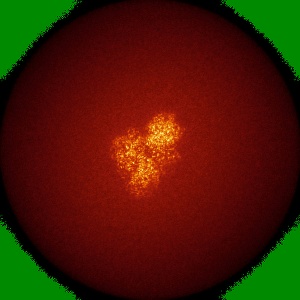

Cryo-EM structure of CAK in complex with inhibitor dinaciclib

Single-particle1.9 Å

Sample: CDK-activating kinase

High-resolution cryo-EM of the human CDK-activating kinase for structure-based drug design.